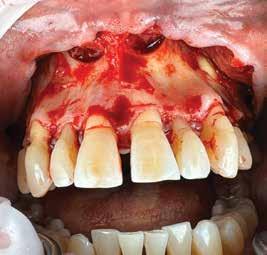

72 FDC 2026 Speaker: Full Arch Implant Reconstruction in the Digital Era: Past, Present and Future